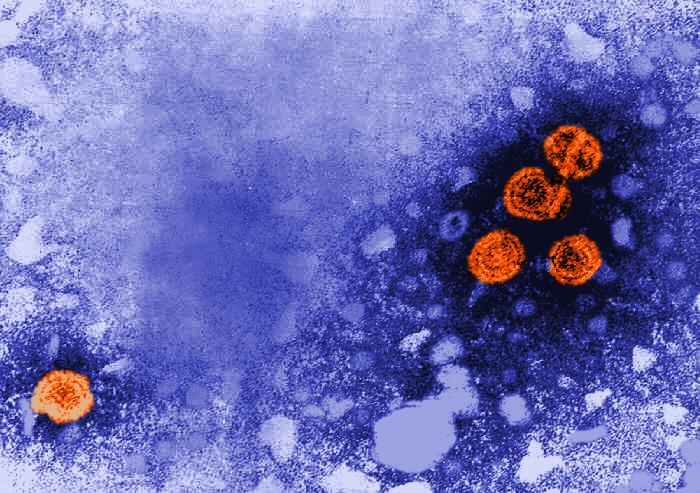

Hepatitis B

Hepatitis B is a viral infection that attacks the liver. It spreads through blood and bodily fluids, including from mother to baby during birth, and it behaves very differently depending on when a person contracts it. Adults who get hepatitis B usually clear the infection on their own, but babies almost never do. According to data from Johns Hopkins and the CDC, as many as 9 in 10 infants infected in their first year of life will develop chronic, lifelong infection. Up to 25% of those chronically infected will eventually die from liver failure or liver cancer, often decades after the initial infection with no symptoms in between. The damage happens slowly and silently, which is part of what makes the virus so dangerous in young children.

Doctors gave the vaccine at birth for more than 30 years precisely because of this timing issue. Waiting even a few months creates a window of vulnerability, and vaccinating only infants born to mothers known to be infected has already failed as a strategy in the U.S. Doctors still don’t screen about 15% of pregnant people for the virus, according to CDC data. So infected mothers slip through undetected every year. Routine vaccination effectively eliminated chronic hepatitis B in young American children. The virus still circulates, with over 17,000 chronic cases diagnosed in 2023 alone. But those cases are now concentrated in adults who were never vaccinated.